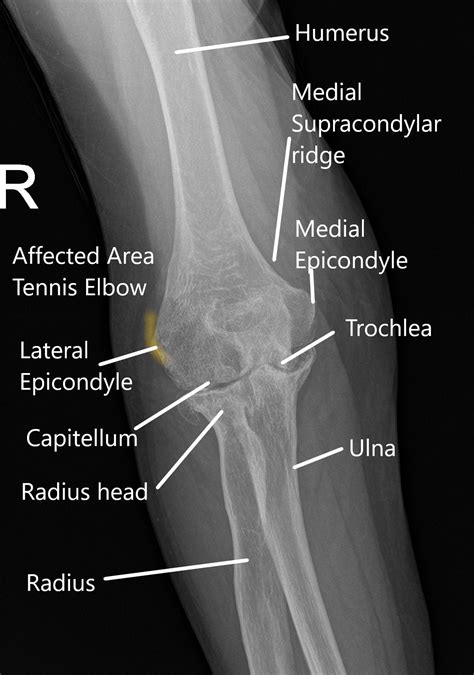

Alright, first things first: what exactly is tennis elbow? It’s formally known as lateral epicondylitis. This condition causes pain on the outer part of your elbow where the tendons of your forearm muscles attach. It’s often caused by overuse or repetitive motions, like those involved in… you guessed it… playing tennis! But don’t let the name fool you – it can affect anyone, from avid gardeners to office workers who spend hours typing. When you have tennis elbow, the tendons become inflamed or even develop small tears. The pain can range from a mild ache to a sharp, debilitating sensation that makes everyday tasks challenging. Now, why do we need x-rays? X-rays are a type of imaging test that uses electromagnetic radiation to create pictures of the inside of your body. Think of them as a quick snapshot of your bones. In the case of tennis elbow, the primary purpose of an x-ray isn’t usually to diagnose the condition itself, because it does not show soft tissues such as tendons. Instead, x-rays are more useful for ruling out other potential causes of your elbow pain. They can help your doctor spot things like bone spurs, arthritis, or fractures that might be mimicking the symptoms of tennis elbow. So, while an x-ray might not directly show the inflammation in your tendons, it’s a valuable tool in the diagnostic process. It helps your doctor get a complete picture of your elbow and determine the best course of treatment for you. This comprehensive approach ensures that your treatment plan is tailored to your specific needs and the underlying cause of your pain. If the x-rays come back clear, it strongly suggests that the pain is indeed due to soft tissue damage, which further points to tennis elbow. This is a very common scenario.

What X-Ray Views Reveal and What They Don’t

Alright, let’s get into the nitty-gritty of what an X-ray can and can’t show when it comes to tennis elbow . As we mentioned earlier, the primary purpose of an x-ray in this case isn’t to diagnose tennis elbow directly. Since tennis elbow is a soft tissue injury, the x-ray images won’t show the tendons or the inflammation that’s causing your pain. So, what can you see? An x-ray is excellent at visualizing the bones of your elbow. It can reveal any fractures, dislocations, or bone spurs. These are bony growths that can develop due to overuse or arthritis. It can also show signs of arthritis, which can cause pain and stiffness in the elbow. Although the x-ray cannot directly show tennis elbow, it helps your doctor to rule out other possible causes of your pain. If the x-ray images come back clear, it helps your doctor narrow down the diagnosis and focus on the likelihood of a soft tissue injury like tennis elbow. Other diagnostic tests like an MRI or ultrasound are better suited for visualizing soft tissues like tendons. When it comes to treatment, x-rays don’t typically directly affect the treatment plan for tennis elbow. X-ray results primarily help to ensure that the treatment plan is safe, effective, and correctly addresses your pain’s source. If the x-ray reveals a fracture or a bone spur, your doctor might need to adjust the treatment plan accordingly. If the x-ray is clear, it reinforces that the problem lies with your soft tissues, and the doctor can focus on therapies to address the tendon issue. Remember, an X-ray is one piece of the puzzle. Your doctor will use the results of the x-ray, combined with your physical examination, medical history, and potentially other imaging tests, to create a comprehensive treatment plan for your tennis elbow.